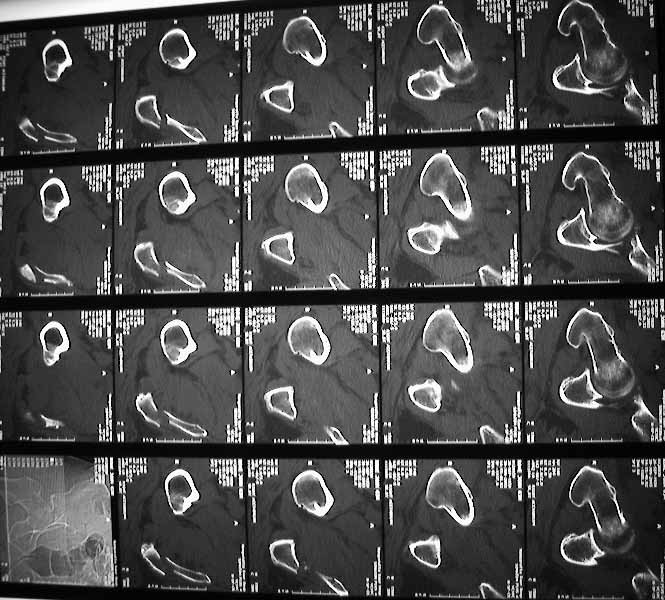

63 year old male, simple fall 4 days ago with an undisplaced Right Surgical neck of humerus fracture and this acetabular fracture. My assessment is that it is an anterior wall & column fracture with a blow out of the quadrilateral plate. the posterior column is intact. I see the immediate options as an attempted closed reduction and traction or an open reduction. I am right in saying this would need to be openly reduced through an ilioinguinal approach (which I have never seen or done). Or do I wait and do his Total Hip Replacement when his fracture has healed?